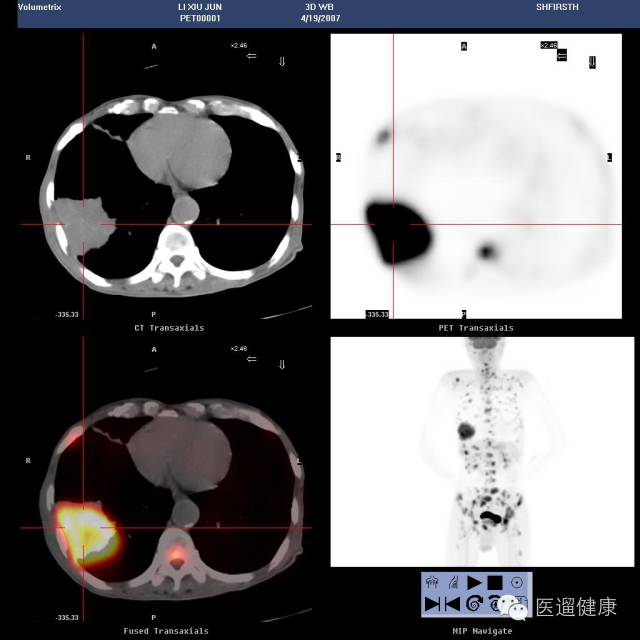

病患:男,75岁,“咳嗽、咳痰伴左骶髂关节疼痛半月”CT平扫:右下肺占位。PET/CT检查目的:肺部病灶定性、了解全身情况。

右肺下叶软组织肿块,边缘分叶状,与右下胸壁相连,放射性浓聚,SUV最大值11.3

隆突下LN肿大,放射性分布浓聚,SUV最大值6.2

肝内多发大小不等结节状低密度区,放射性浓聚,SUV最大值9.8

骶骨骨质破坏,放射性浓聚,SUV最大值11.1

医生通过PET/CT检查得出结论:

右肺癌伴纵隔淋巴结、肝脏、骨转移(IV期)